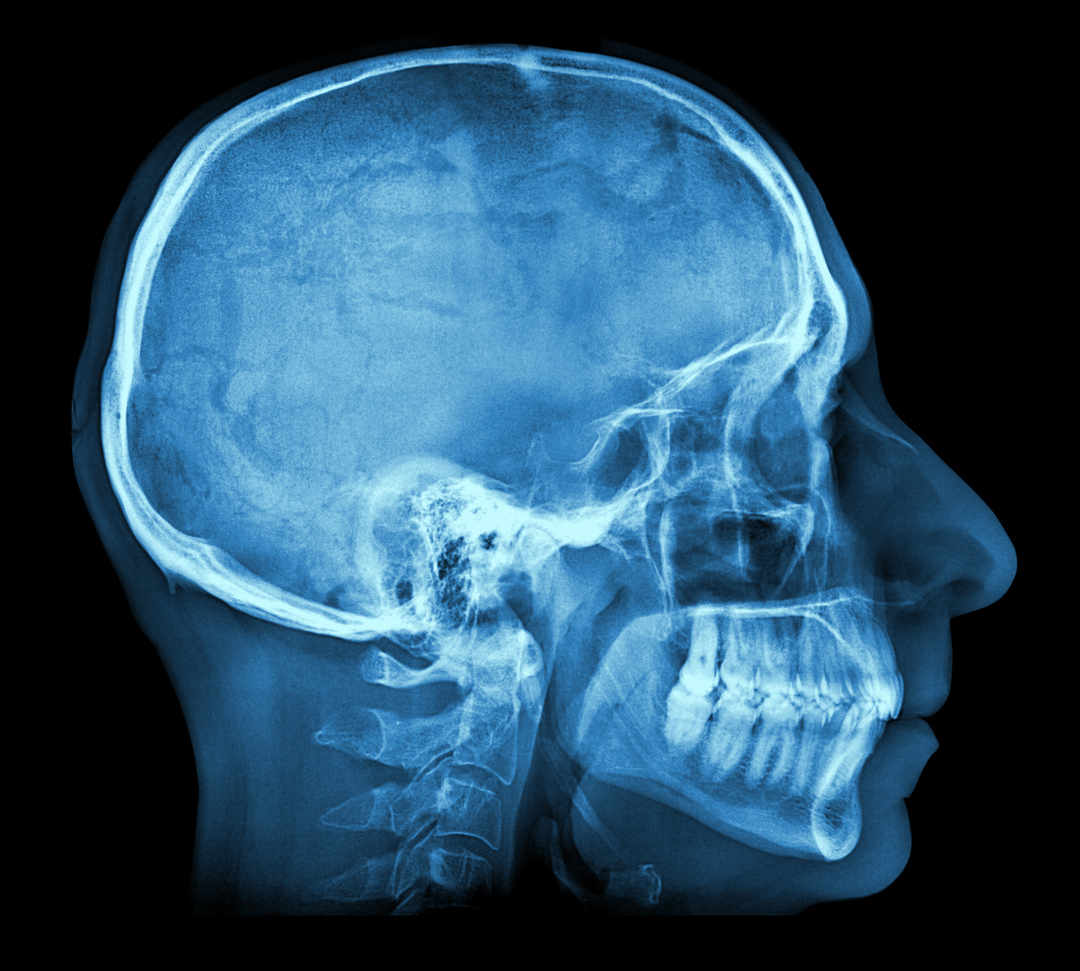

Anne Baecher vous présente un nouveau moyen pour faire parler les morts: l'imagerie forensique.

Cette technologie permet d’éviter d’ouvrir le corps pour visualiser une hémorragie mortelle, évaluer la force d’un impact, définir la trajectoire d’une balle ou encore déceler une erreur médicale.

Reportage en compagnie de Silke Grabherr, médecin légiste et cheffe de clinique à l’Unité de médecine forensique du Centre universitaire romand de médecine légale de Lausanne.